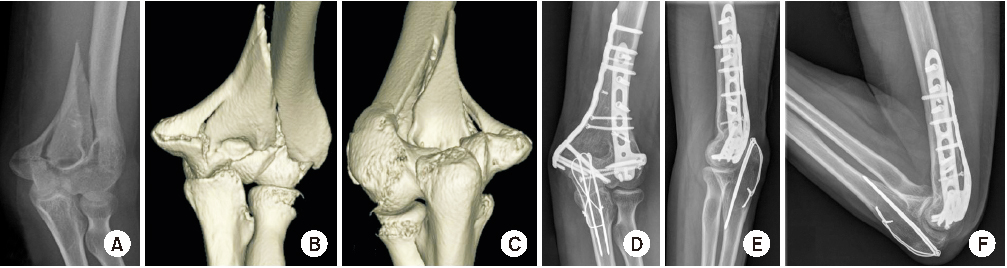

Fig. 7

Type 4 fracture. (A, B) Preoperative X-ray showed small metaphyseal bony fragment. (C, D) Three-dimensional computed tomography. (E, F) Small bony fragment was fixed with miniplate for simplifying fracture pattern, then reduced other fragment.